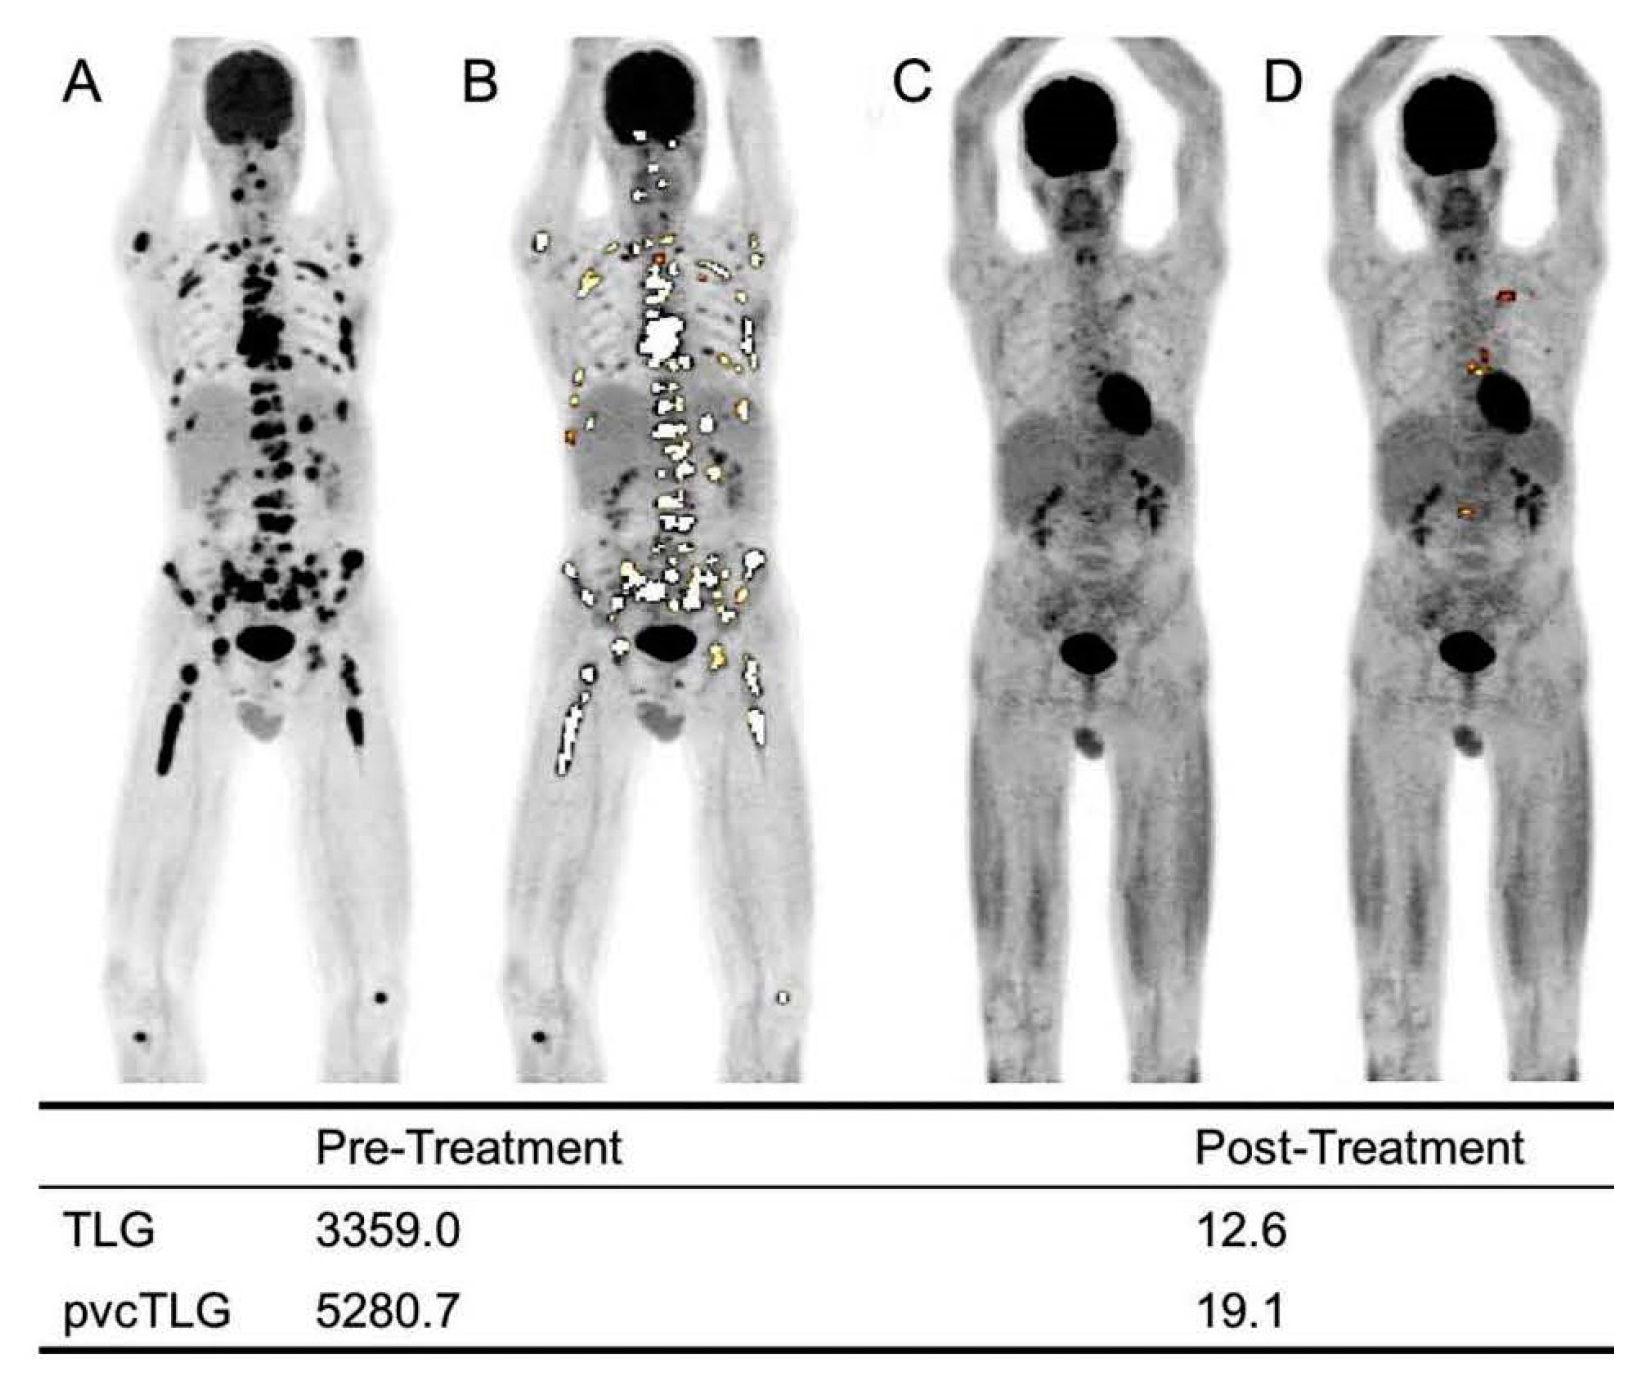

10. [18F]FDG PET Quantification

13. AI for PET Quantification

| FDG PET Quantification | Mostly Research | Quantification using [18F]FDG PET in MM is generally challenging. While SUVmax has proven to be more effective than other PET metrics for this application, it only reflects metabolic activity in a limited region. Although MTV and TLG are employed as volumetric PET metrics, their effectiveness can be reduced due to the presence of numerous lesions in some cases. Some institutions are now leaning toward CT-based segmentations; these techniques are consistently reproducible, yet their clinical patient assessment merits further study. The IMPetus approach offers another perspective, primarily visual-based. While this method is thorough, its effectiveness can be influenced by the expertise of the individual interpreting the results. |

| AI for PET Quantification | Research | The AI approach to evaluate PET results in myeloma using this new concept has shown encouraging outcomes thus far. The investigators argue that this method can address the challenges associated with inconsistent evaluations of PET results in patients with myeloma. |